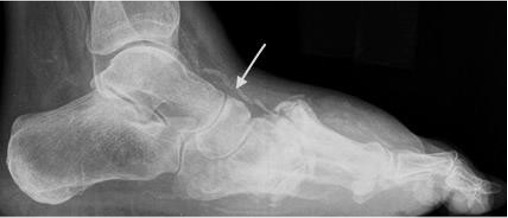

Diabetic Charcot foot centred at TMT joints with dense sclerotic bone, bony debris and dislocation. Note vascular calcification (arrow).

Fig 1: Osteomyelitis at calcaneal pressure point with marrow epicentre, cortical destruction and adjacent soft tissue ulcer.

Fig 2: Charcot midfoot with articular (TMTJ) epicentre, sclerotic bone fragments (arrows) and no soft tissue ulcer